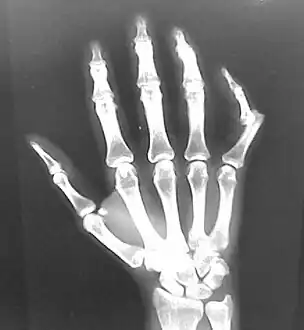

Dislocation of the left index finger

Radiograph of right fifth phalanx bone dislocation

Radiograph of left index finger dislocation

Dislocation of the carpo-metacarpal joint.

Radiograph of right fifth phalanx dislocation resulting from bicycle accident